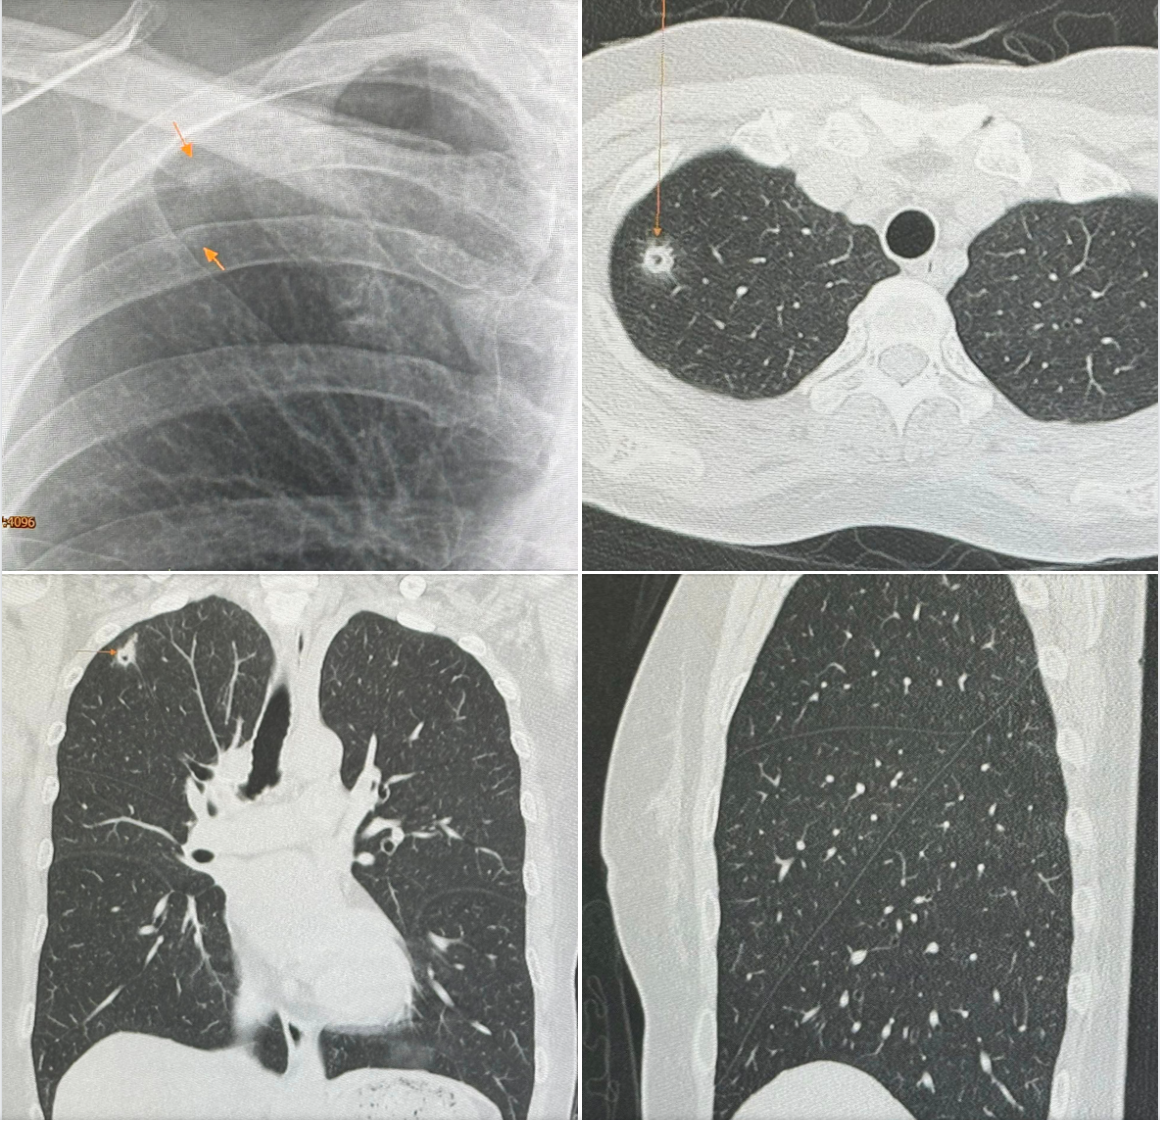

ไปตรวจร่างกายประจำปี วันที่ 12 พฤษภาคม 2567 เอกซเรย์ปอดพบก้อนเล็กๆเกิดขึ้นใหม่ที่ปอดขวากลีบบน เอกซเรย์ปอดก่อนหน้านั้น 1 ปีปกติ ทำคอมพิวเตอร์ปอดพบก้อนขนาด 0.9 × 0.9 × 1.7 เซนติเมตร เห็นโพรงอยู่ข้างในก้อนที่ปอดขวากลีบบน ตรวจเลือดไม่ติดเชื้อเอชไอวี

ผู้ป่วยไปรับการผ่าตัดปอดเอาก้อนจากปอดขวากลีบบนออกที่โรงพยาบาลใกล้บ้านเมื่อวันที่ 22 พ.ค. เพราะสงสัยมะเร็งปอด ผลพยาธิวิทยาเป็นปอดอักเสบจากเชื้อราคริปโตคอคคัส ตรวจเลือดหาคริปโตคอคคัสแอนติเจนหลังผ่าตัด 4 วันให้ผลบวก titer 1:8 แพทย์เริ่มให้การรักษาด้วยยา fluconazole ผู้ป่วยมาขอคำแนะนำหลังจากนี้ควรทำอย่างไรต่อไป

ซักประวัติ มีนกพิราบอยู่แถวบ้านหลายตัว ให้อาหารนกพิราบประจำ ผู้ป่วยรายนี้หายใจสปอร์ของเชื้อราคริปโตคอคคัส นีโอฟอร์แมนส์ (Cryptococcus Neoformans) จากมูลนกพิราบเข้าไปในปอด ทำให้เกิดปอดอักเสบเป็นก้อนที่มีโพรงข้างใน